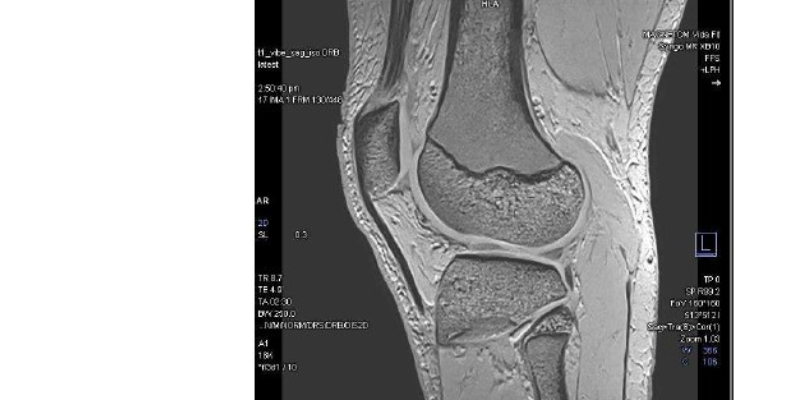

Canopy Imaging is proud to announce the installation of the MAGNETOM Vida Fit, a state-of-the-art 3T MRI system from Siemens Healthineers, at its Ormiston Canopy Imaging Clinic in Auckland. This achievement not only provides quicker, more precise scans for patients but also delivers on our commitment to sustainable healthcare.

The MAGNETOM Vida Fit also brings advanced AI-driven imaging and a patient-friendly design, offering exceptional diagnostic capabilities across neurology, oncology, musculoskeletal, and cardiovascular care. Features such as BioMatrix and Deep Resolve ensure consistent, high-quality results with reduced scan times, whilst the latest coil technology enhances patient comfort.